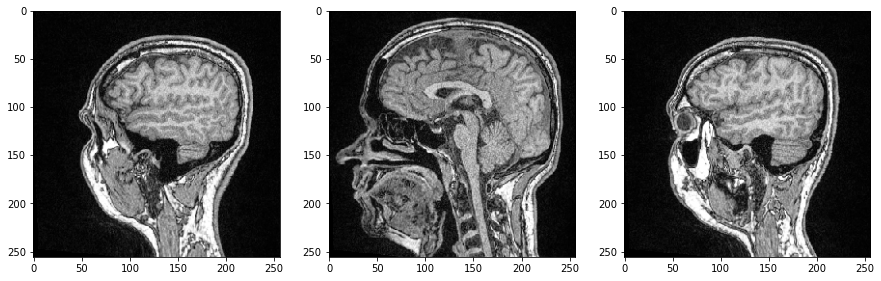

Podemos inspeccionar cortes individuales de la imagen especificando su índice en nuestro array 3D de numpy y esta vez usar el imshow de Matplotlib para la visualización:

import matplotlib.pyplot as plt

fig, axs = plt.subplots(1, 3, figsize=(15,15))

# show three planar images

axs[0].imshow(image_stack[48], cmap='Greys_r')

axs[1].imshow(image_stack[96], cmap='Greys_r')

axs[2].imshow(image_stack[144], cmap='Greys_r');